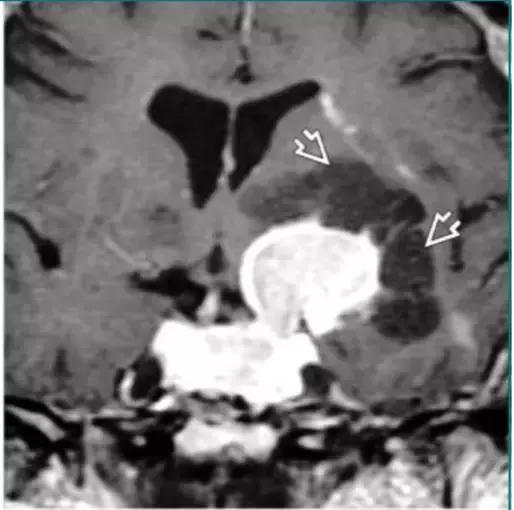

神经脑囊虫病